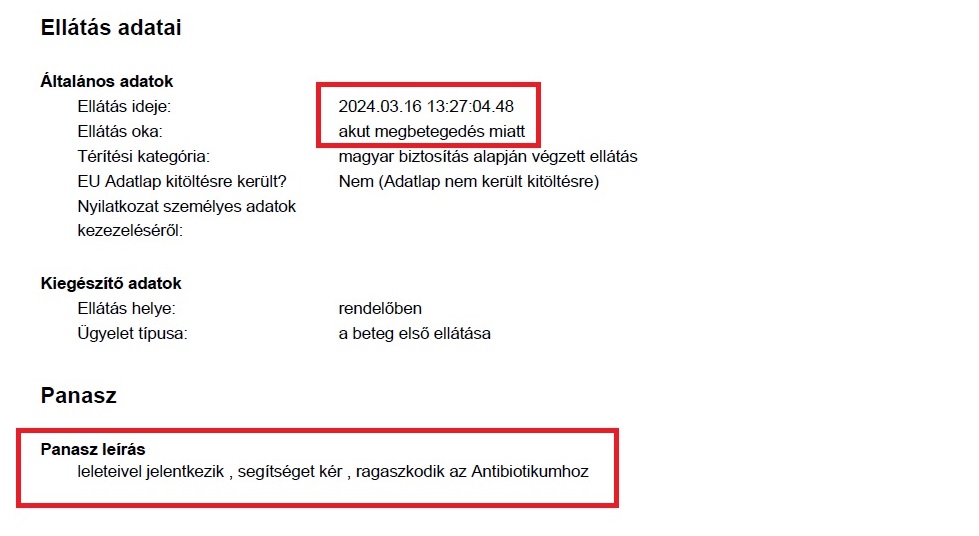

13./ Március 16 – Tatai Ügyelet – Könyörgés antibiotikumért a kezeletlen vesemedence-gyulladásra

Bent voltunk hetek óta az ország fővárosának I. számú Belgyógyászati Klinikáján, Nefrológiáján és végig súlyos állapotban kezeletlenül hagyták a fiamat. Egy ámokfutás volt, amit velünk csináltatott Ledó Nóra, hogy a fiam kezelést kapjon. Ismét a helyi ügyeletre mentünk. Ennek ambuláns lapja rögzíti is, hogy a fiam már szinte könyörög kiszolgáltatottan a segítségért.